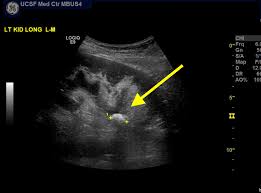

Kidney Stone Ultrasound Break Up. The doctor uses an x ray or ultrasound to find the stone or stones in your kidney. Yes doctors are starting to use ultrasound called lithotripsy to break up kidney stones rather than resorting to surgery if they can t be passed.

Specific ultrasound imaging mode optimized to visualize kidney. Works by focusing high energy shock waves to break up kidney stones. A noninvasive procedure that uses shock waves to break up the kidney stone into.

Ultrasound can break up kidney stones.

Then they aim high energy shock waves at your kidney from the outside. Percutaneous nephrolithotomy pnl is a type of surgery to break apart and. The kidneys are located in the abdomen in the retroperitoneal area. Most techniques involve inserting a disintegrating device through the bladder to break up the blockage.